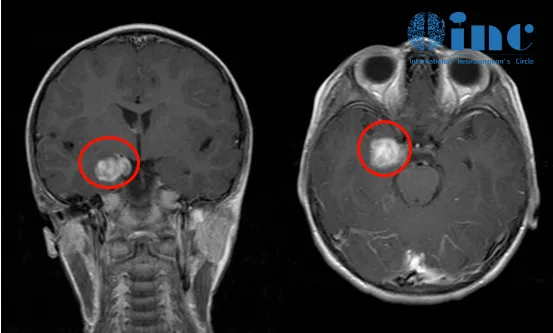

Jimmy一开始接受外科手术时只有7岁,内侧颞叶肿瘤使他在复杂部分癫痫发作时会出现严重的意识障碍和精神症状,他会短暂地失去意识,四肢抽搐,还会不断重复自己癫痫发作前的动作,流口水、吞咽、走路等,这些使他无法正常生活和学习,因此选择接受外科手术。开颅行经侧裂入路为其行切除手术,术后7年均未发作。

术前影像

之后,艾文父母带着孩子来到了SickKids就诊,在核磁共振成像扫描下,可以清晰地看到艾文脑内左枕叶部肿瘤占位,后经影像学分析,考虑为左枕叶毛细胞性星形细胞瘤。原来改变这的元凶是艾文患了“脑胶质瘤”。